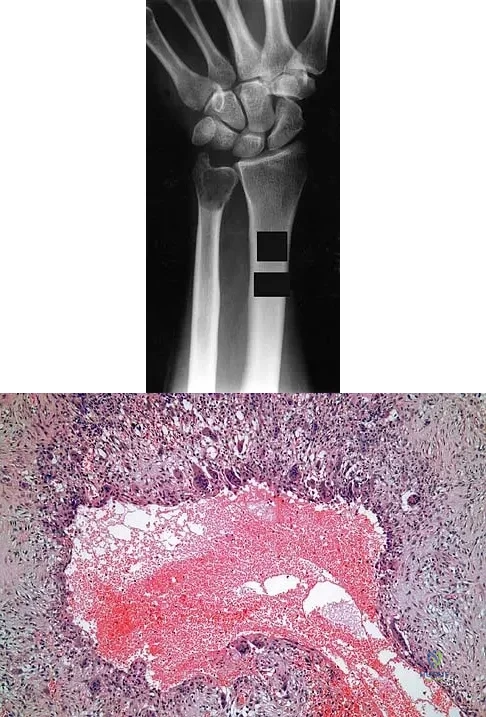

A 30-year-old patient has wrist pain. A radiograph and biopsy specimen are shown in Figures 34a and 34b. What is the most likely diagnosis?

Explanation